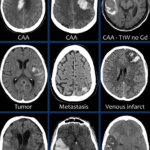

뇌출혈은 출혈 위치에 따라 뇌 실질 내 출혈, 지주막하 출혈, 뇌실 내 출혈 등으로 구분된다. 이 중 가장 흔한 형태는 뇌 실질 내 출혈로, 만성 고혈압이 주요 원인이다. 지주막하 출혈은 뇌동맥류 파열로 발생하는 경우가 많으며, 갑작스럽고 극심한 두통이 특징이다. 출혈이 발생하면 뇌압이 급격히 상승하고 주변 뇌세포가 손상돼 의식 저하, 마비, 언어 장애 등 심각한 신경학적 결손으로 이어질 수 있다.

의료계는 뇌출혈의 ‘골든타임’을 수 시간 이내로 본다. 증상 발생 후 빠르게 영상 검사를 시행하고 출혈 부위와 원인을 파악해야 생존율을 높이고 후유증을 줄일 수 있다.